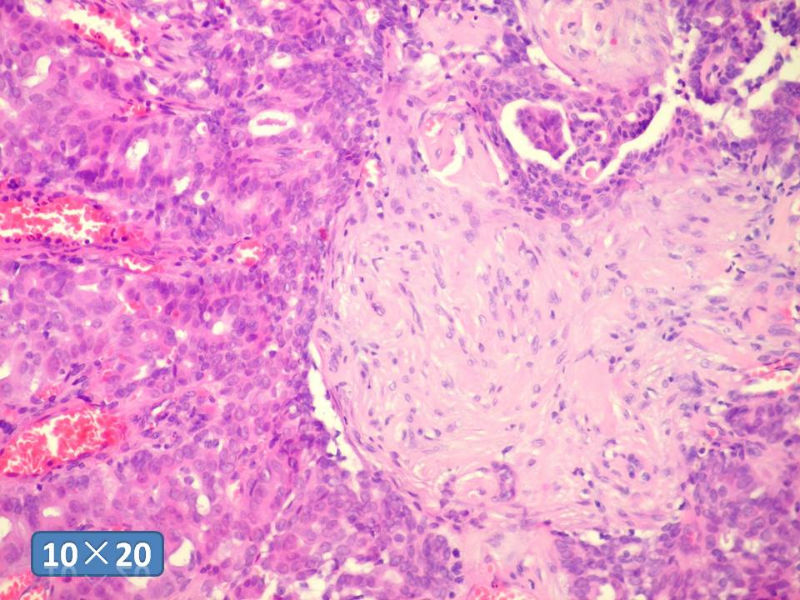

只能说是乳头状瘤

是不是导管内

乳头状瘤 and 导管内乳头状瘤 are the same; Benign lesion.

After you work up and you still cannot be sure it is benign , atypical or maignant lesion, you can call 乳头状lesion.

If this is excisonal case, you should figure out the nature of the papillary lesion.